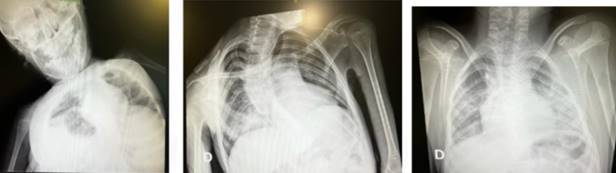

Tres niños requirieron ingreso a UCI: uno por neumonía en portador de toracopatía, otro instaló un estado de mal epiléptico y el tercero por síndrome inflamatorio multisistémico (MISC) con fenotipo tipo Kawasaki. No hubo fallecimientos.

Figura 3: Radiografía de paciente COVID con neumonía.